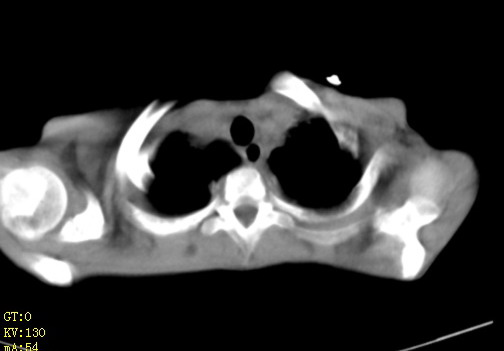

女,12岁,气促、咳嗽2天,3个月前查胸片示:两肺感染,急诊入院查ct,血常规等未检查。

双肺中下野不规则片絮状阴影,中外带明显,双侧胸腔少量积液,心影增大,心腔密度减低,隆突下及左侧气管旁见钙化淋巴结影,考虑双肺感染、心衰;建议结合临床除外h1n1并急性心衰,先心不能排除。

两肺多发片絮状模糊影,以下肺外带居多,内见支气管气像,纵膈窗未减影,两侧胸腔积液,心影增大,结合心超,支持重症肺炎,非常时期,甲型h1n1流感不排除。